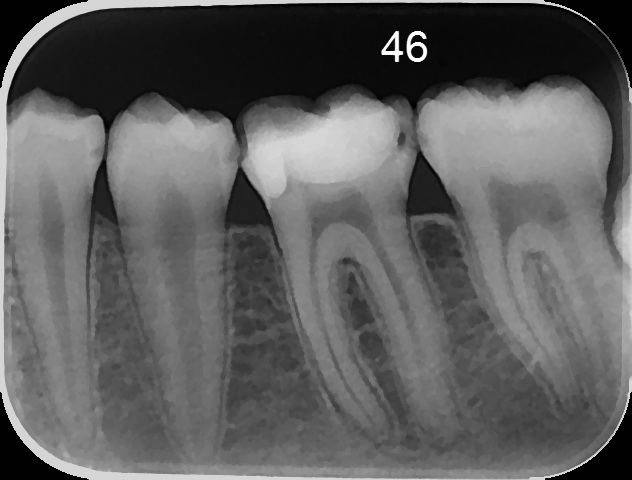

СЛИКЕ